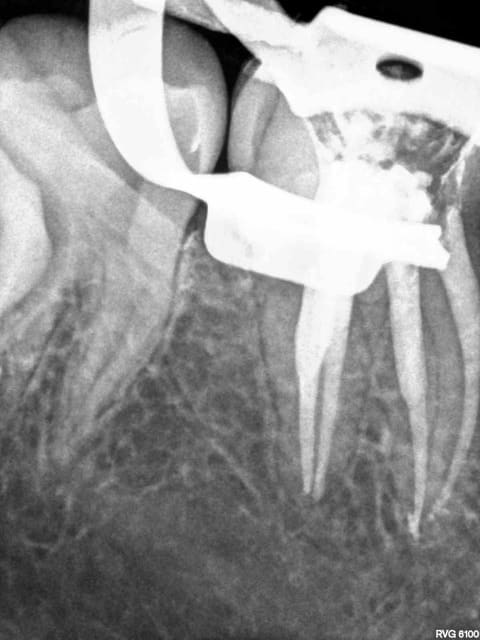

C'est quoi la proba d'avoir une deuxième bio à 5 canaux en 2 semaines?

(la radio excentrée est dégueulasse, mais ça montre les doubles courbures, quelques peu minimisées par l'angulateur...